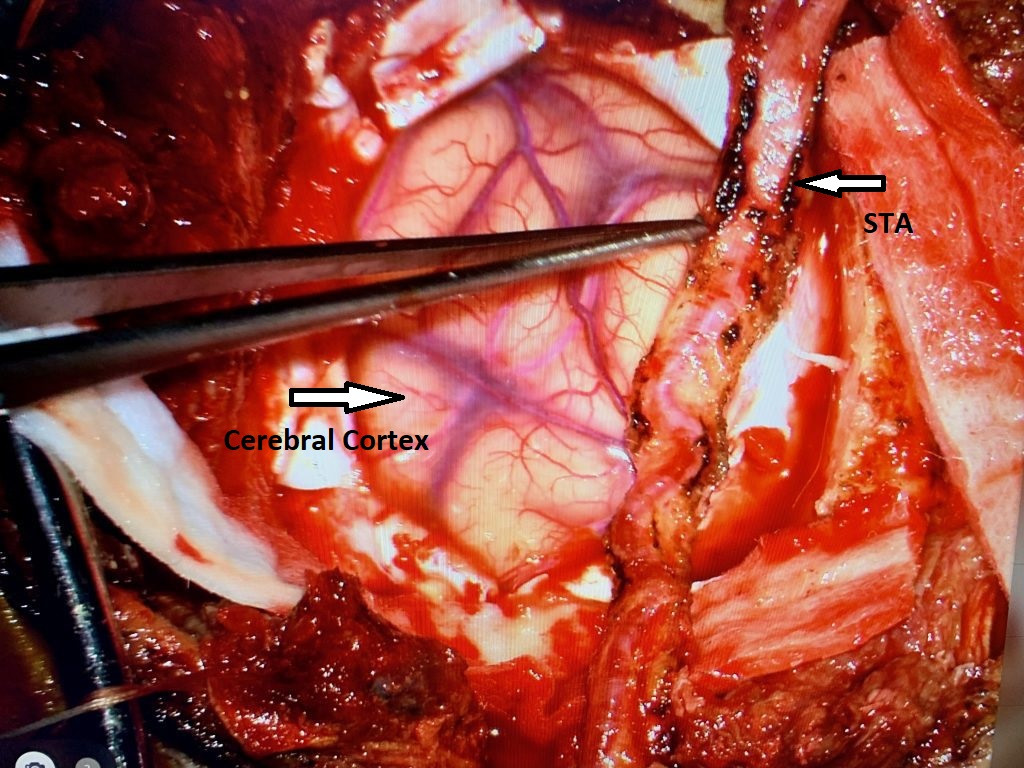

Endovascular:

CME:

Symptomatic Near-Occlusion of the Carotid Artery

Author: Jonathan L. Brisman M.D., F.A.C.S., Read More!